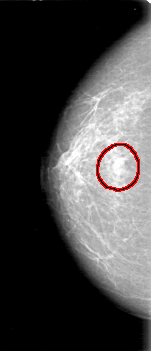

D_4027_1.RIGHT_CC

RIGHT_CC LINES 5251 PIXELS_PER_LINE 2251 BITS_PER_PIXEL 12 RESOLUTION 43.5 OVERLAY

FILE: D_4027_1.RIGHT_CC.OVERLAY

TOTAL_ABNORMALITIES 1

ABNORMALITY 1

LESION_TYPE MASS SHAPE OVAL MARGINS OBSCURED

ASSESSMENT 0

SUBTLETY 3

PATHOLOGY BENIGN

TOTAL_OUTLINES 1

BOUNDARY